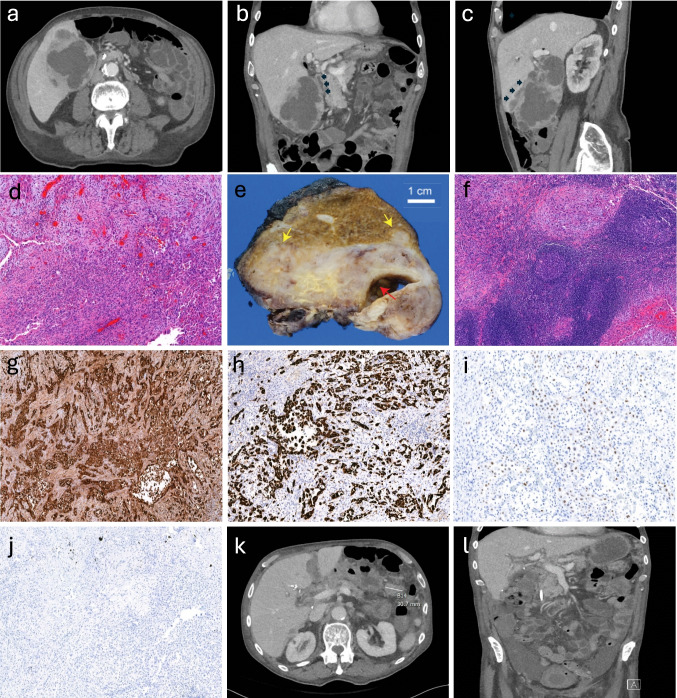

Purpose: Gallbladder squamous cell carcinoma (SCC) is a rare subtype of gallbladder malignancy, comprising only 1-4% of cases. Ectopic expression of β-human chorionic gonadotropin (β-hCG) has been described in various epithelial cancers and is associated with aggressive behavior. We report the first known case of gallbladder SCC with diffuse β-hCG expression and markedly elevated serum β-hCG levels, aiming to explore its clinicopathological implications and potential as a prognostic biomarker.

Methods: We present the clinical, radiologic, surgical, and pathological findings of a patient with a large gallbladder mass. A literature review was conducted to contextualize our findings.

Results: The patient underwent open cholecystectomy with hepatic segment IVb/V resection. Final pathology revealed poorly differentiated SCC with acantholytic features and diffuse β-hCG immunoreactivity. Two metastatic lymph nodes were identified in the low hepatoduodenal nodal basin. Postoperative serum β-hCG was significantly elevated. Despite surgical resection, the patient experienced rapid disease recurrence and progression.

Conclusion: This case represents the first documented instance of β-hCG-expressing gallbladder SCC. Diffuse β-hCG expression may reflect a dedifferentiated and aggressive tumor phenotype associated with early metastasis and poor prognosis. Further studies are warranted to investigate the prognostic and biological significance of β-hCG in gallbladder SCC and its potential role as a biomarker.